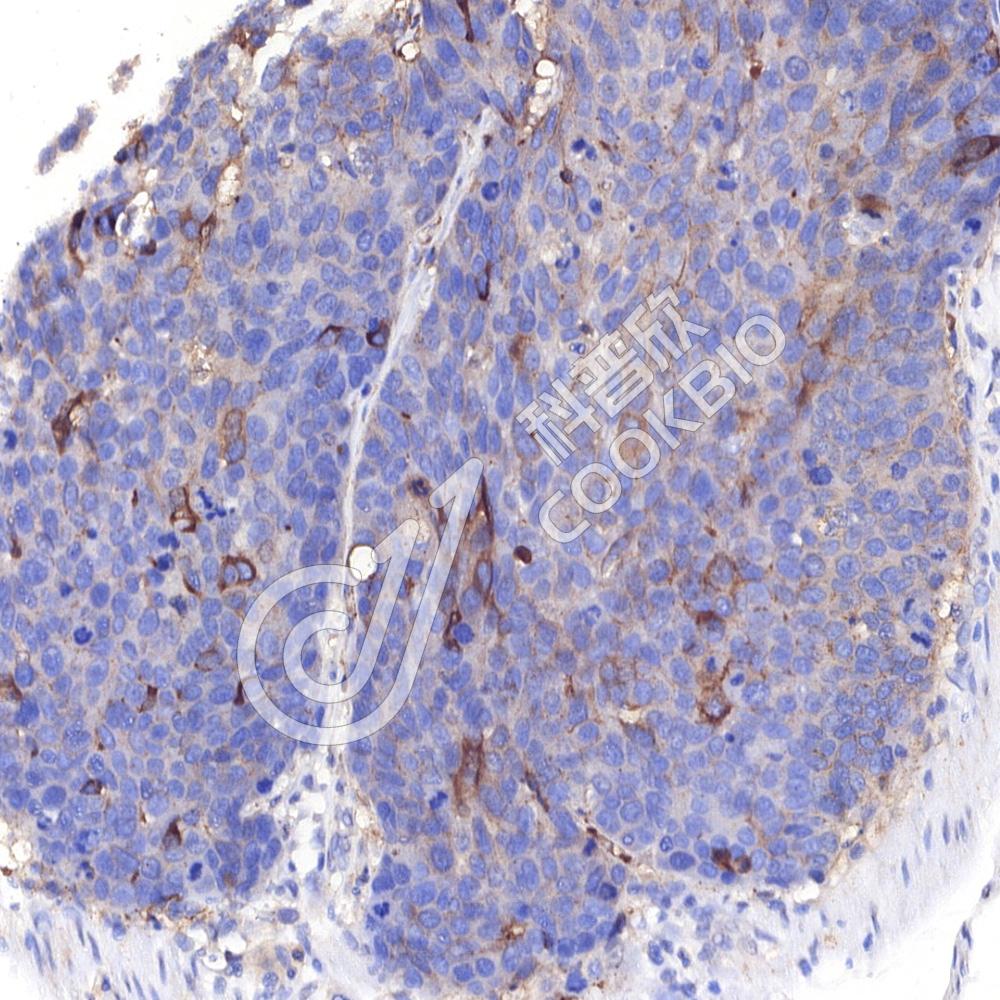

IHC检测Phospho-Tau(S202/T205)蛋白(货号 K5450180).

样品: 小鼠阿尔茨海默氏症脑模型, 4%多聚甲醛 (货号KSG1101) 固定12-24小时.

抗原修复: 柠檬酸抗原修复液(干粉, pH 6.0) (KSG1201), 高压锅均匀喷气计时2分钟.

—抗: 1: 300稀释, 4℃ 孵育过夜.

二抗: S-vision免疫组化多聚二抗(山羊抗兔),即用型 (货号KB3906), 室温孵育20分钟.